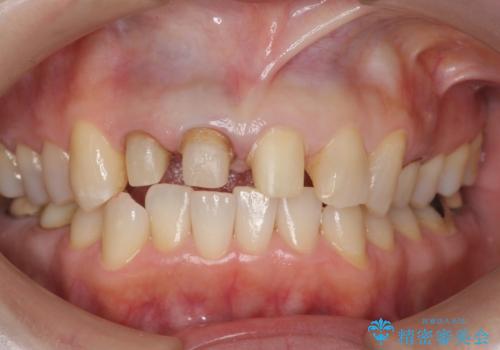

前歯のすき間 以前よりも広がってきた 二度と広がらないようにしたい セラミック治療

- 前歯のすき間を気にして来院。

右上2本を以前セラミックにしたが、前歯のすき間が広がってきてしまったとのこと。

右上の前歯のみの被せなおしですと、右上の前歯が反対側に比べて極端に大きくなってしまうことを説明し、左上の前歯も併せてセラミックにすることにしました。